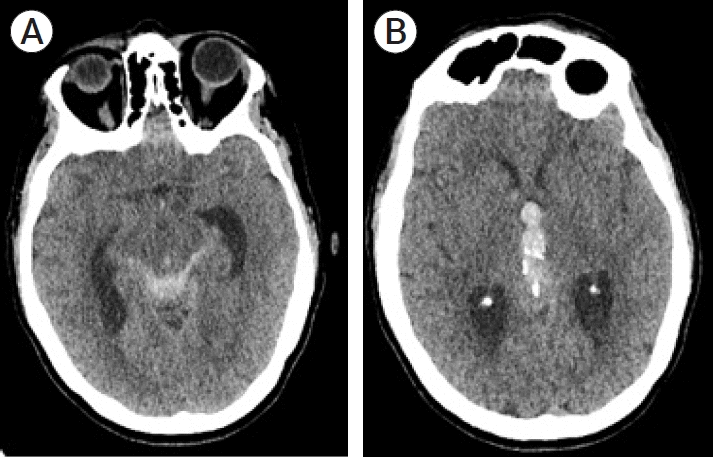

A 64-year-old lady with no past medical history presented with sudden onset headache, vomiting, and altered level of consciousness (Glasgow Coma Scale (GCS) E3V4M6). Her initial computed tomography (CT) scan showed predominantly intraventricular haemorrhage (IVH) with associated hydrocephalus, as well as subarachnoid blood in the ambient and quadrigeminal cisterns (Fig. 1a). A large 15 mm calcified pineal gland was noted within the blood clot (Fig. 1b). A CT angiogram (CTA) did not show a vascular abnormality and haemorrhage into a pineal tumour was the working diagnosis. She was intubated for transfer to our neurosurgery unit, underwent external ventricular drain (EVD) insertion and was extubated after 2 days on neuro intensive care with the EVD removed on day 4.

Fig. 1.

(A) Unenhanced CT taken at presentation with slices through the tectum, (B) Unenhanced CT taken at presentation with slices through the calcified pineal gland. CT, computed tomography